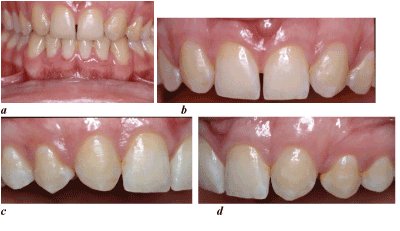

Figure 3a-d. After orthodontic space closure and debonding, a perfect plaque control is required, in order to obtain and maintain a good gingival profile.

The bracket placement in canine substitution cases is different. The bracket is not placed with the incisal edge of the canine as a reference but with the gingival margin as the guide. The gingival zeniths of the lateral incisors should be 0.5 to 1 mm lower than the central incisors, so the canine bracket has to be placed accordingly [15]. To make the final decision if a patient is suitable for the orthodontic approach and to anticipate if additional restorations may be necessary, the authors strongly suggest a carefully executed treatment plan (Figure 4,5).